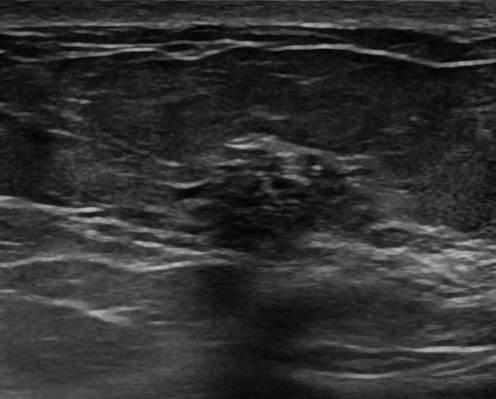

Ung thư vú

Ung thư vú - Ảnh 3

» Thông tin: Nữ giới – 42 tuổi.

» Lâm sàng: Kiểm tra sức khỏe.